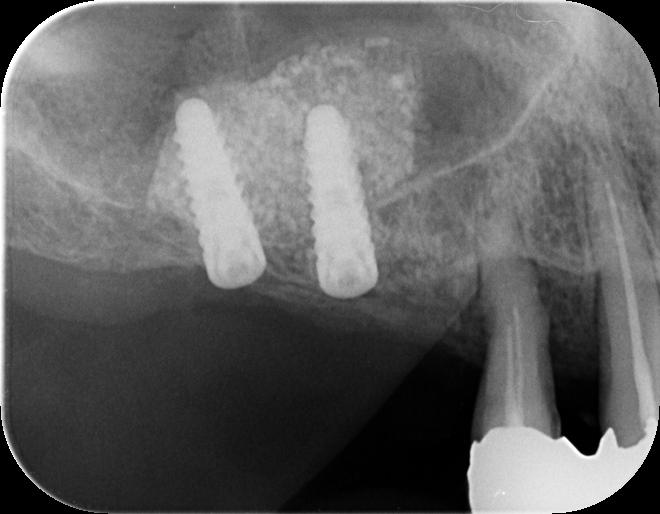

本日はセデーションを行い

ラテラルスリット※1(腫れにくいサイナスリフト)を行いました。オペの成功はスタッフ皆さんのおかげです。いつもありがとうございます。